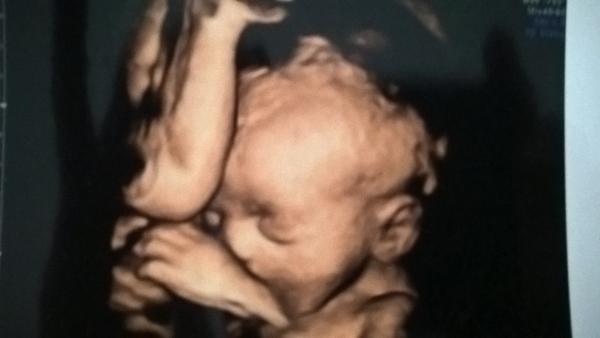

@pavlapavlapavlapavla jeeeee, to je povedená fotečka. A to je vidět ručička té druhé princezny u hlavičky? To je kouzelný ❤

@pavlapavlapavlapavla jé, to je princezna 🙂 A průtoky byly v pořádku? A jak se daří tobě?